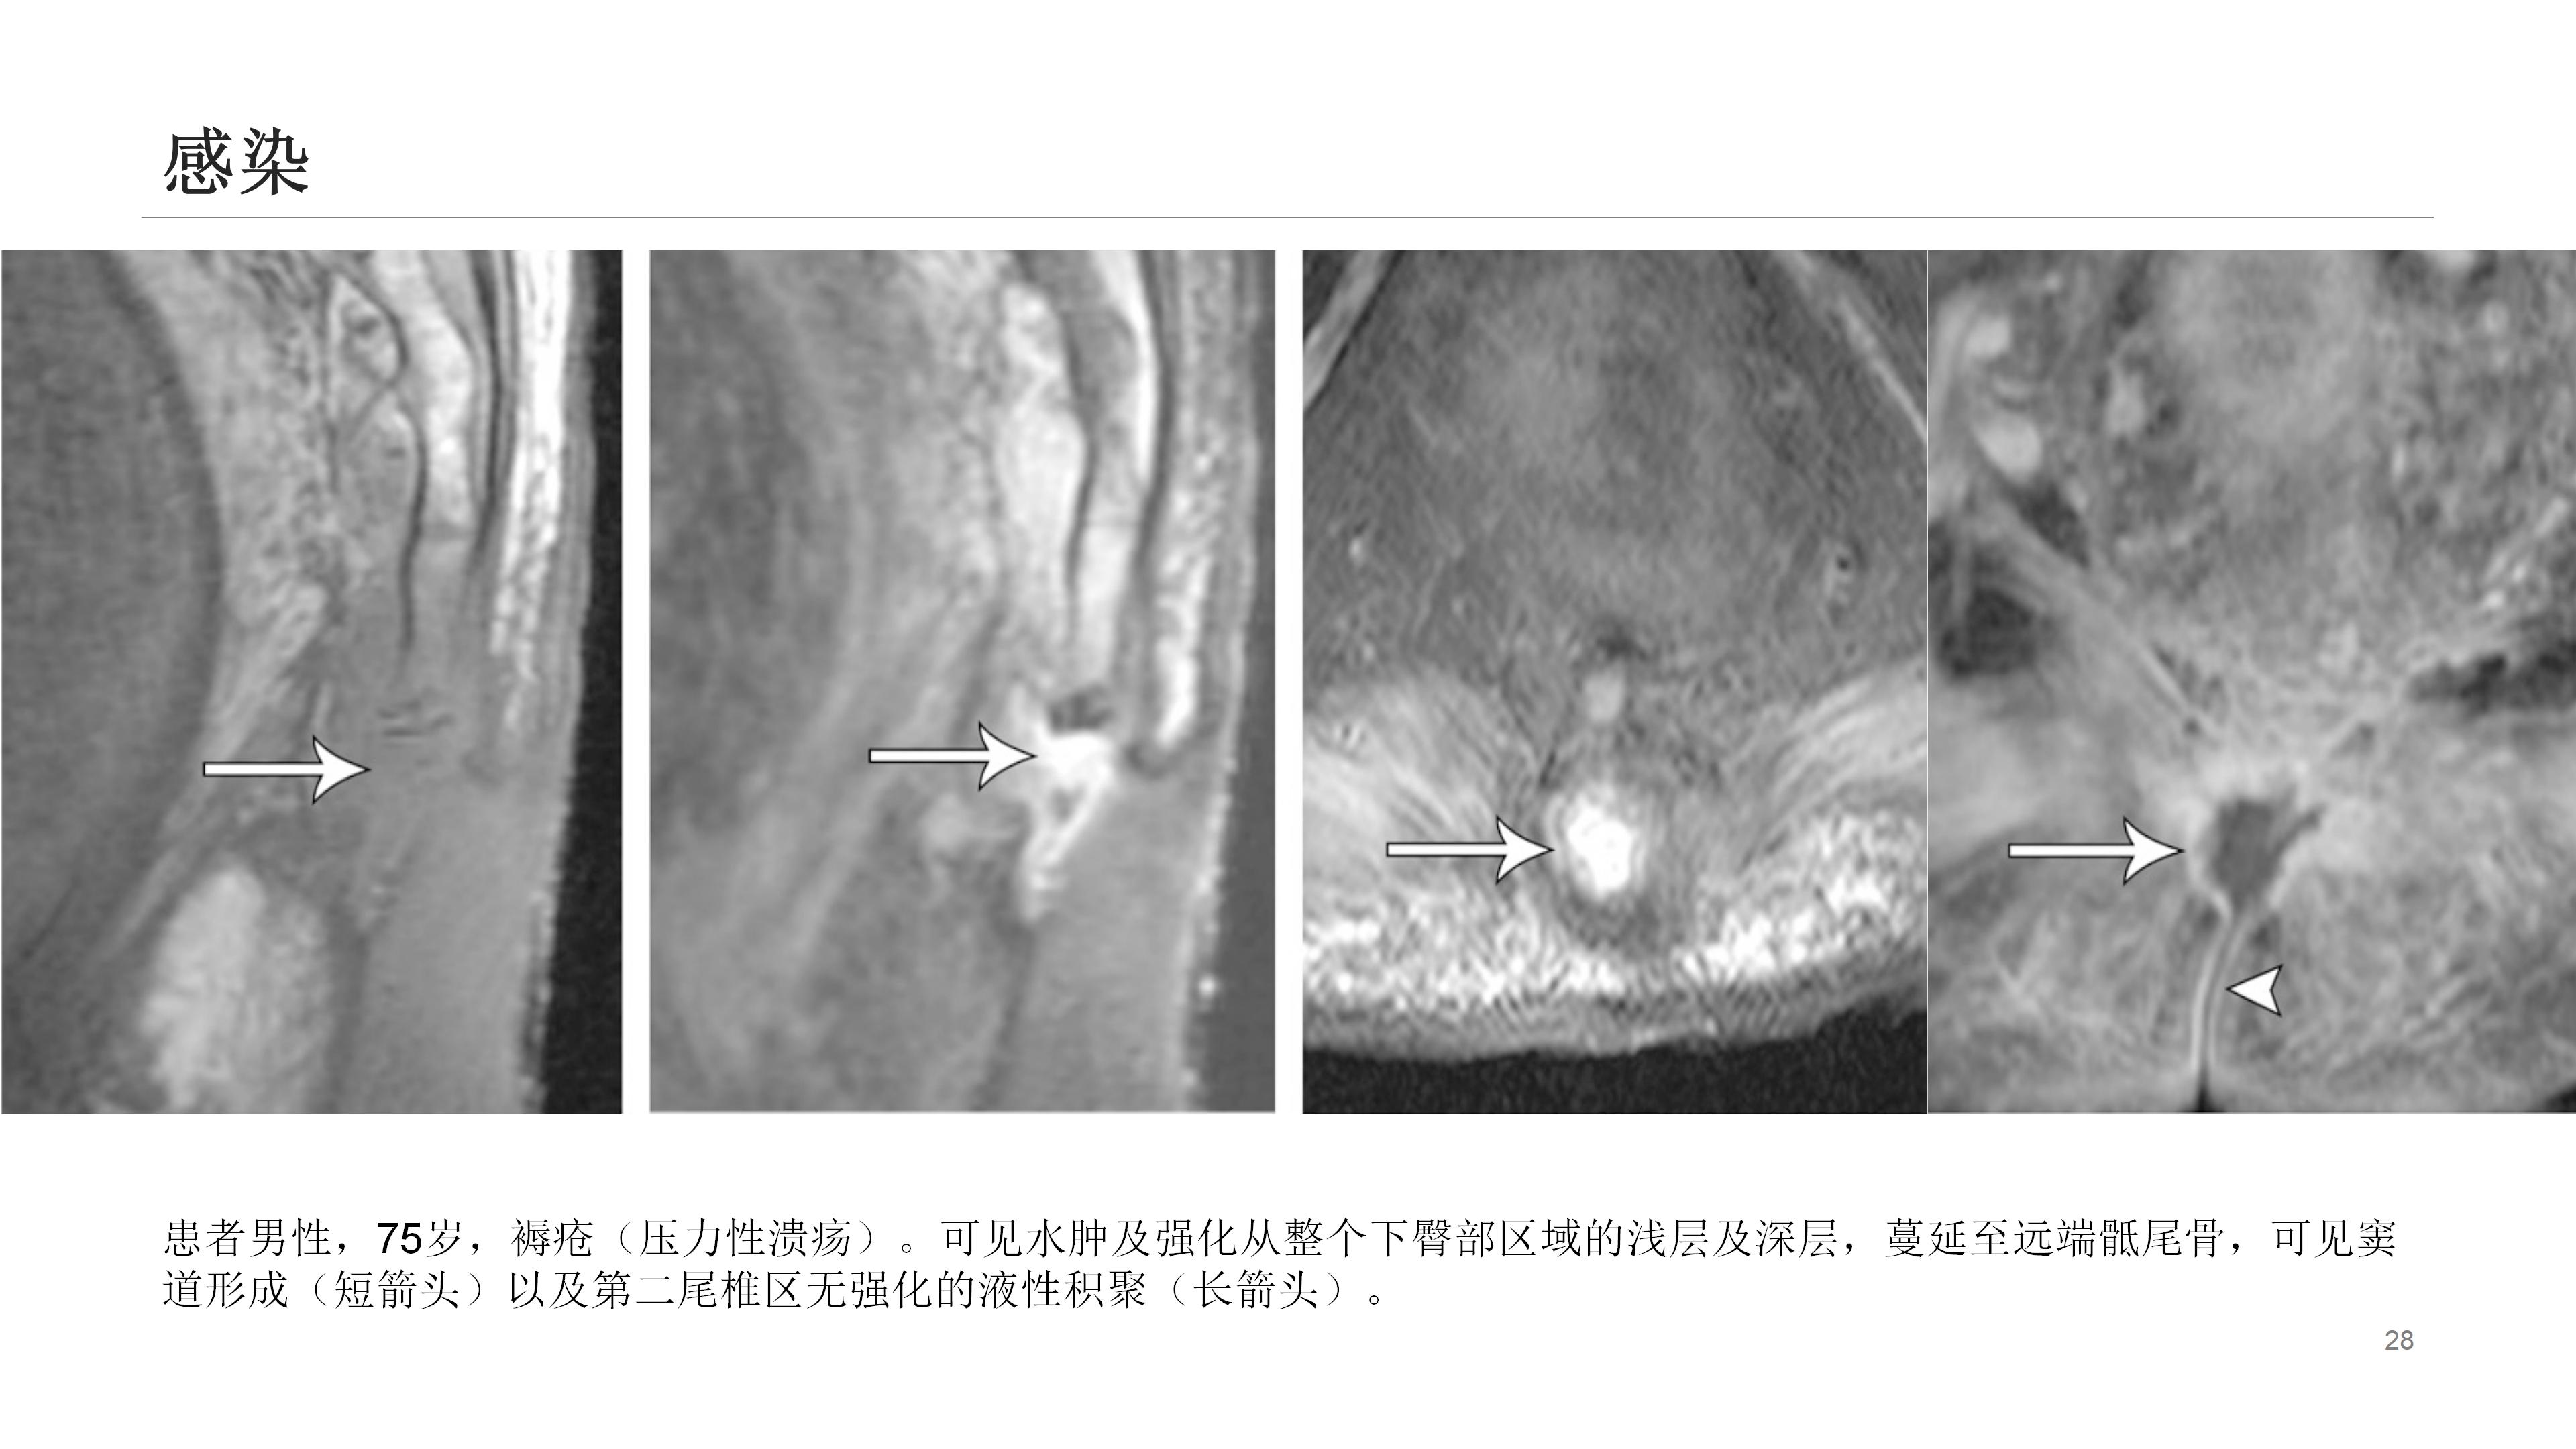

此外,诸如肿瘤、感染、晶体沉积病、囊肿形成(如藏毛囊肿)等其他疾病也可导致尾骨疼痛。